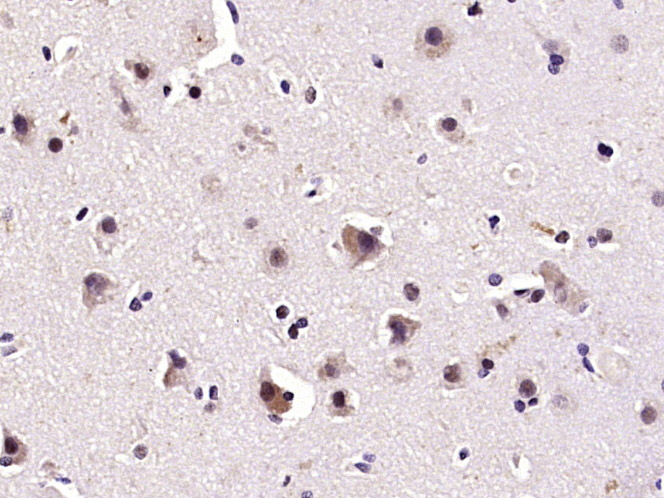

| IHC-P | Human, Rat | Mouse, Pig | 1:100-500 |